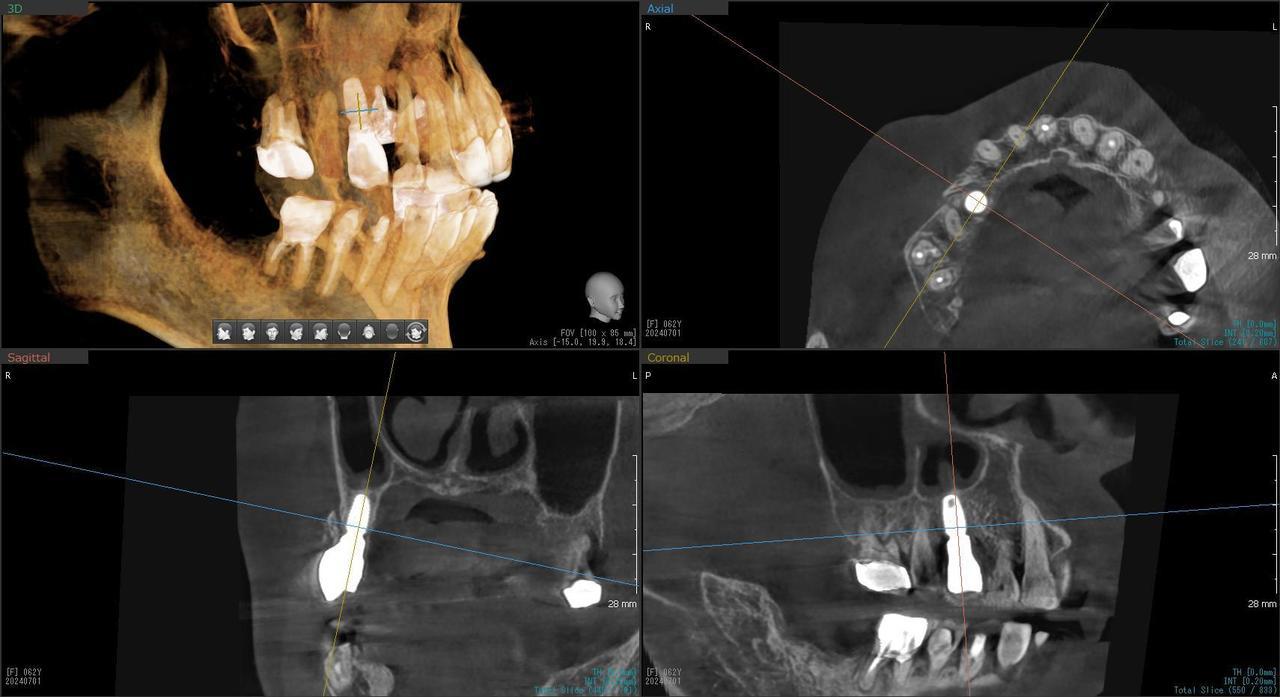

5.右上6番の歯根が破折したに大きな骨欠損を生じたケースに対して、通常なら、大幅な増骨手術(GBRとサイナスリフト)が必要で、最低1年は、かかるケースを、骨補填材なしで、インプラント埋入後、2.5か月で治療を終えたケース

Before

枚方市のインプラントの症例

H・M様 女性 60代

症状としては、左上6番の歯根が歯根が破折したために、炎症が起き、上顎洞底までの及ぶ大きな骨欠損がおきていた、

治療法としては、動揺がひどくなってきて、炎症の症状もあったため、抜歯を希望。抜歯後にインプラント治療を希望したために、CTを撮影したところ、かなりの骨欠損が生じていた。インプラントは不可能か大幅な増骨手術が必要なるようなケースであったが、ご自分の骨が少し残っていた部分にエクストラワイドインプラントで固定をとることと、グラフトレスサイナスリフトを併用する計画を立て、インプラント埋入術を施行。2か月後、インプラントがデータ測定上安定したために、光学印象で印象を行い、2か月半後に上部としてジルコニアクラウンを装着して治療を終えています。

治療結果として、大幅な骨欠損があったが、2か月半という短時間で治療を終えることができた。通常のサイナスリフト等の大幅な増骨手術を行った場合、患者様に、肉体的、金銭的、時間的な負担をかけることになったが、グラフトレスサイナスリフトとエクストラワイドインプラントを使用することにより、そのことを避けることができた。

治療の期間・回数:治療回数インプラント埋入後6回

治療の価格:363000円(税込)

治療費の内訳:インプラント基本料(フィックスチャー(メガジェンインプラントANYONE) 及び手術費用、投薬費用、レントゲン費用、インプラント上部費用(アバットメントおよびジルコニアクラウンの費用用)330000円(税込み)左上6グラフトレスサイナスリフト費用 33000円(税込)